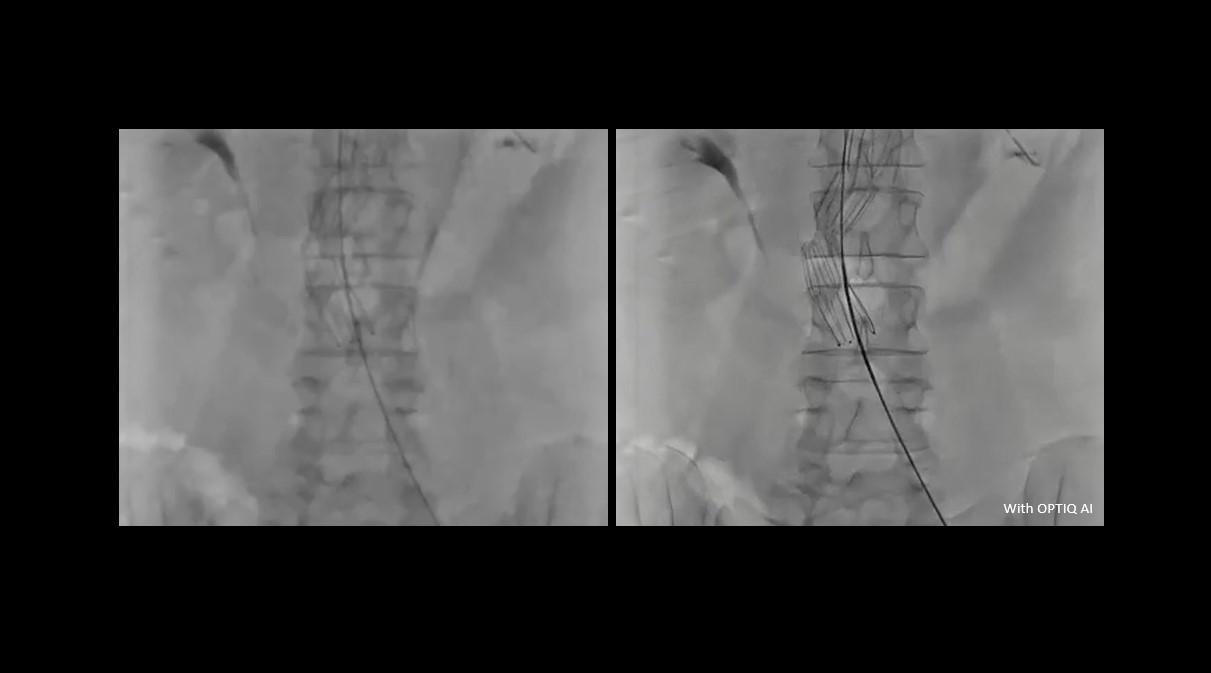

Our Operating room equipment with procedural intelligence technologies is designed to substantiate treatment decisions, enable image-guided therapies supporting ALARA dose, and support infection control measures. From Hybrid ORs dedicated to single surgical disciplines all the way to highly flexible solutions used by multiple surgical disciplines and catering to the versatile needs of a multifaceted case mix. We work together with our solution partners to offer the right solution for you.